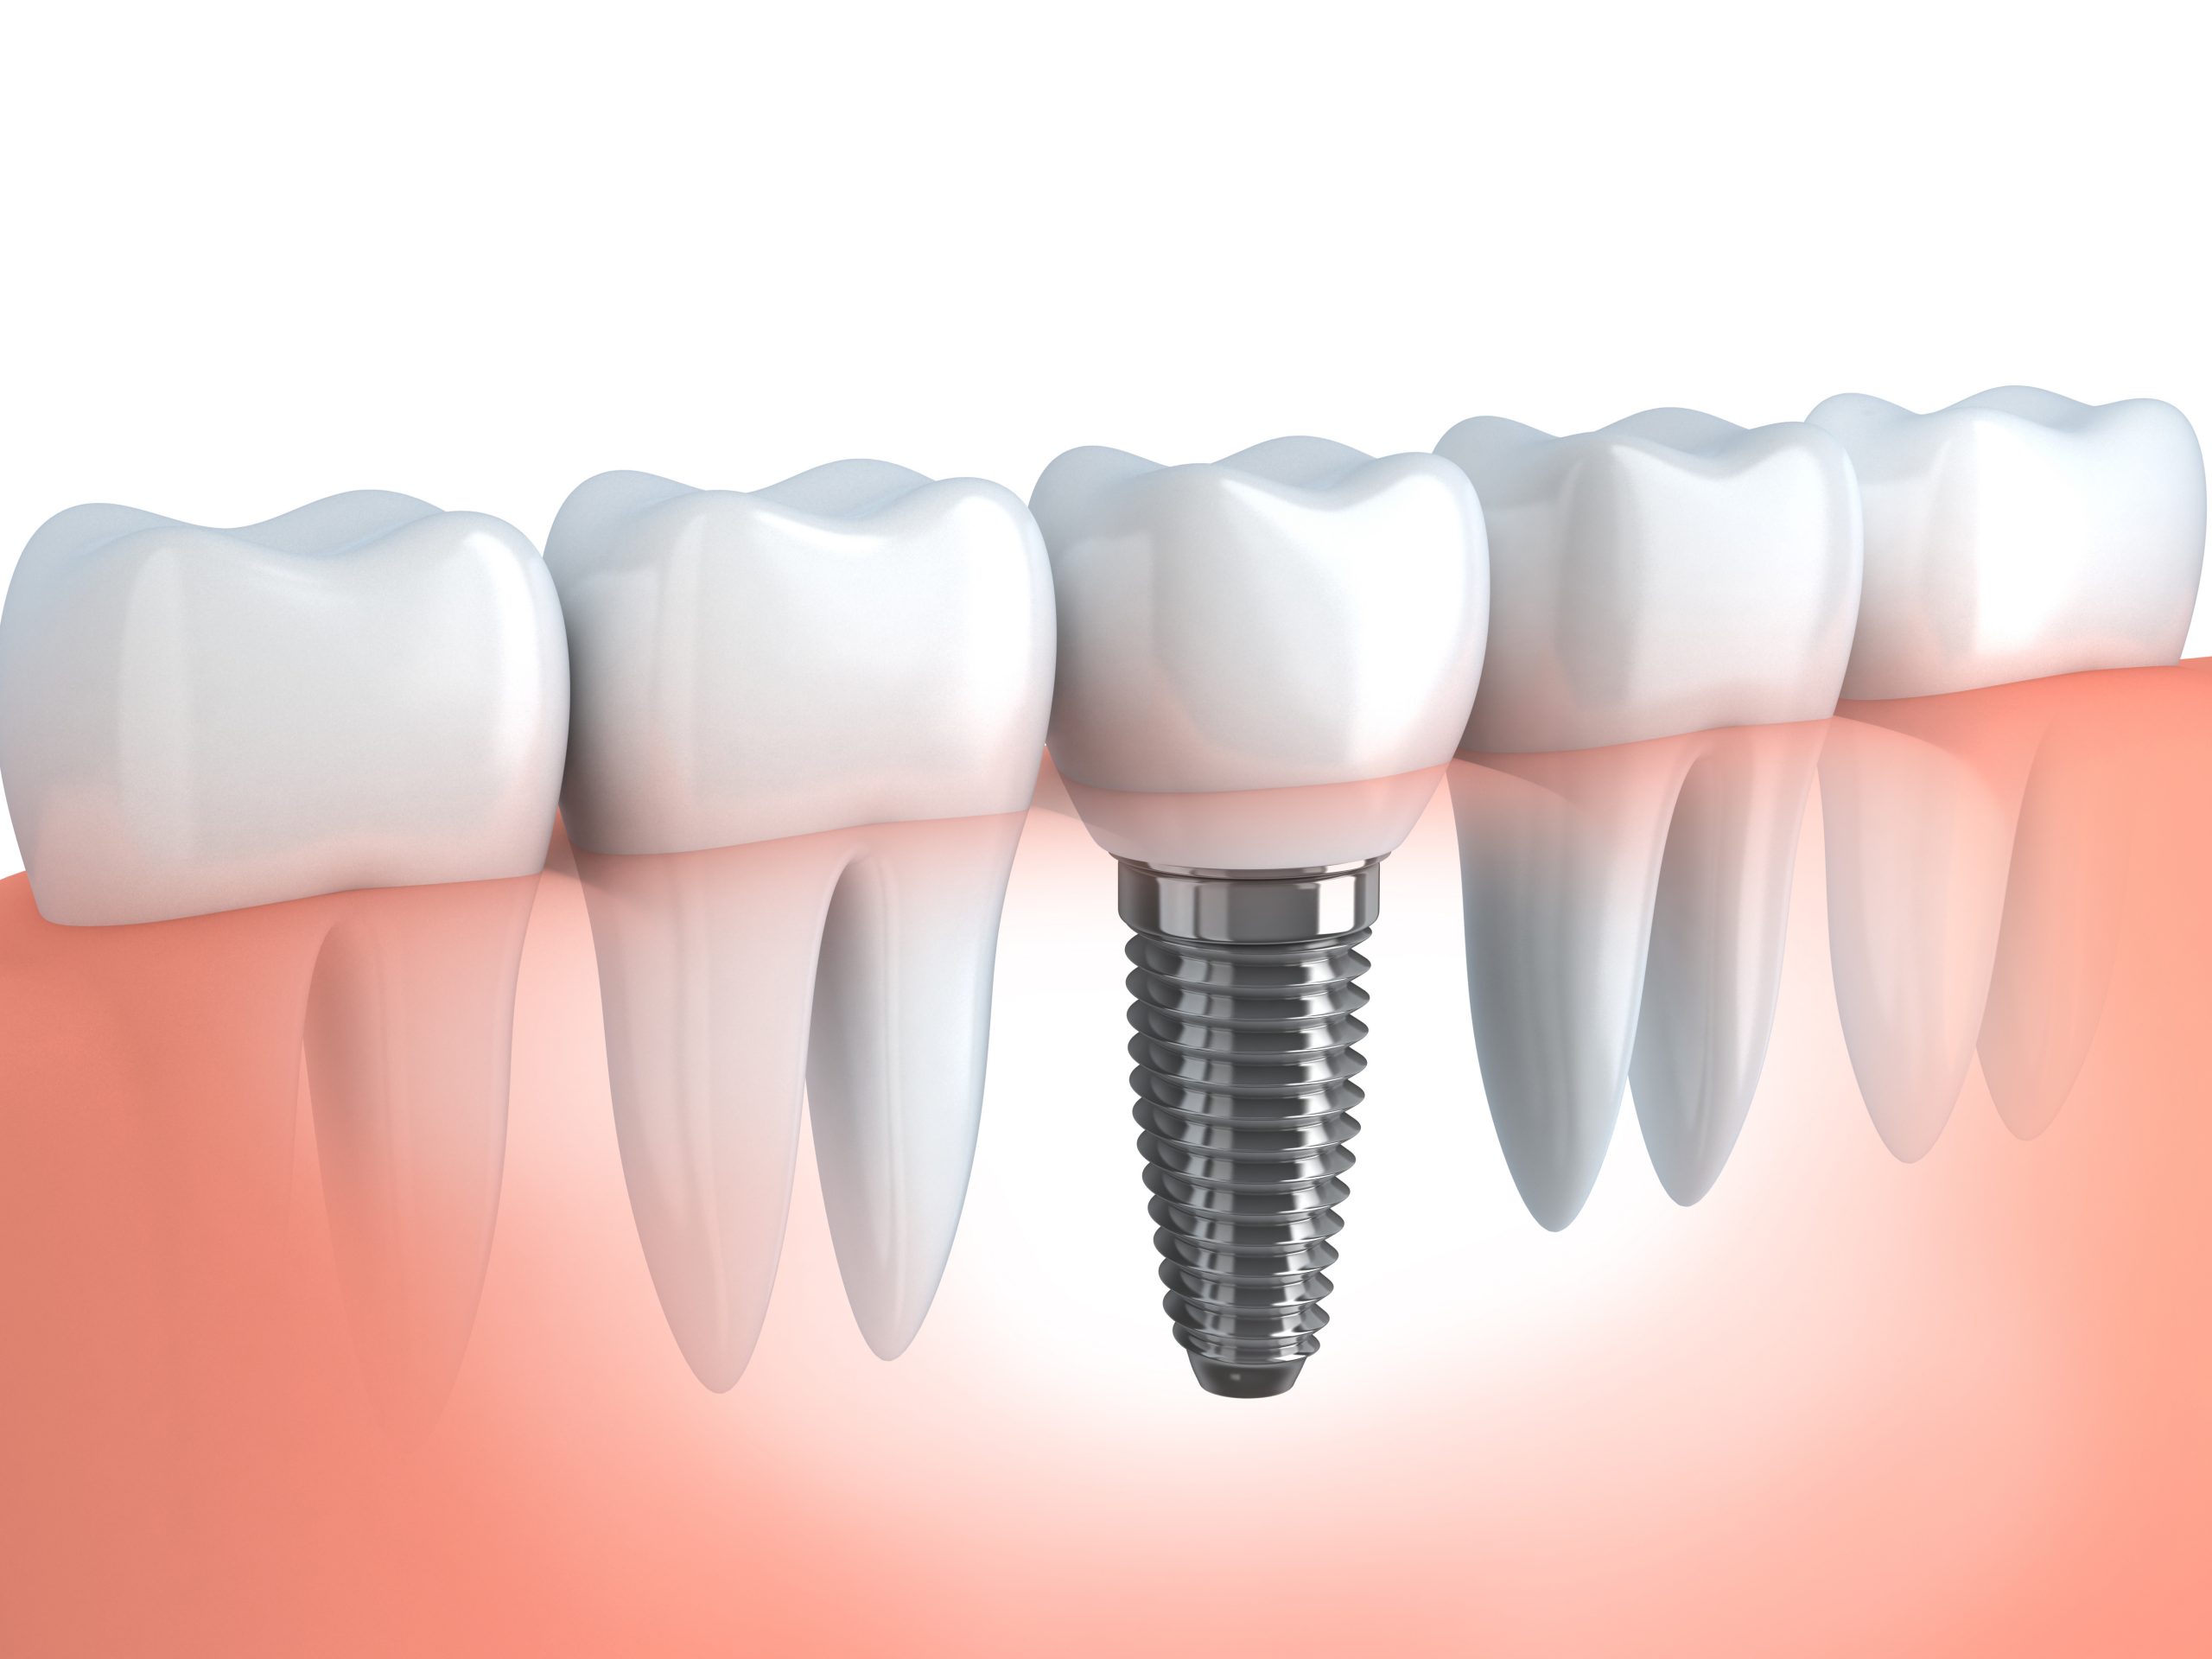

What to Expect During Dental Implant Surgery

You shouldn’t have to live with missing teeth for another second. Dental implants are the “Gold Standard” in tooth replacement technology because they offer a permanent, durable, and natural solution to lost teeth. If you’re considering dental implants, here’s what you should know about the dental implant surgery process. Step 1: Consultation and […]